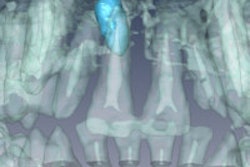

"The tested materials showed a range of distortion degrees," the study authors wrote.

Even so, several were classified as fully compatible, meaning they can be present during an MRI exam even in the tooth of interest, and even if a very precise reconstruction of the tooth surface is required: AH Plus resin-based sealer, glass ionomer cement, gutta-percha, zirconium dioxide, and some composites.

While none of the 3M ESPE composites studied caused any detectable distortions, all of the Ivoclar Vivadent composites in the study caused "significant" artifacts, the researchers noted.

In addition to the Ivoclar Vivadent composites, amalgam, gold alloy, gold-ceramic crowns, titanium allow, and NiTi orthodontic wires were classified as compatible I, meaning the material produces "noticeable distortions" and that acceptance when undergoing MRI depends on the application.

The stainless steel orthodontic appliances and the CoCr sample showed the strongest distortions and were classified as noncompatible, meaning these materials produce strong image distortions even when located far from the imaging region, according to the study authors.